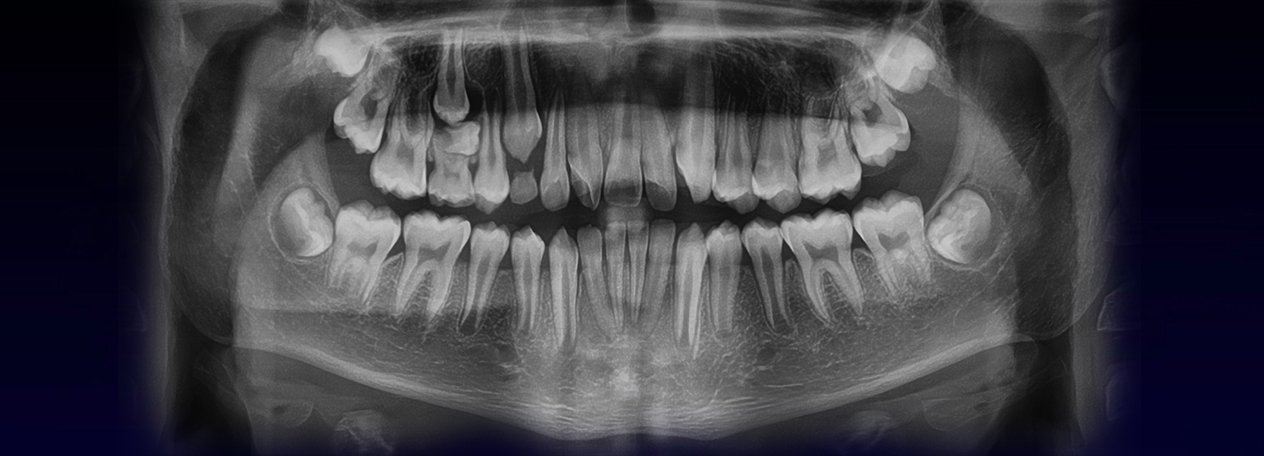

A la evaluación de las radiografías Panorámica, Waters, y radiografía Periapical, observamos, neumatización alveolar y opacificación parcial de seno maxilar izquierdo, lecho alveolar de correspondiente a pieza 2.6, con discontinuidad de la cortical de la pared basal de seno maxilar adyacente, y engrosamiento de la membrana antral de seno maxilar ipsilateral. Signos radiográficos compatibles con proceso inflamatorio sinusal (Sinusitis) en relación a comunicación buco sinusal.